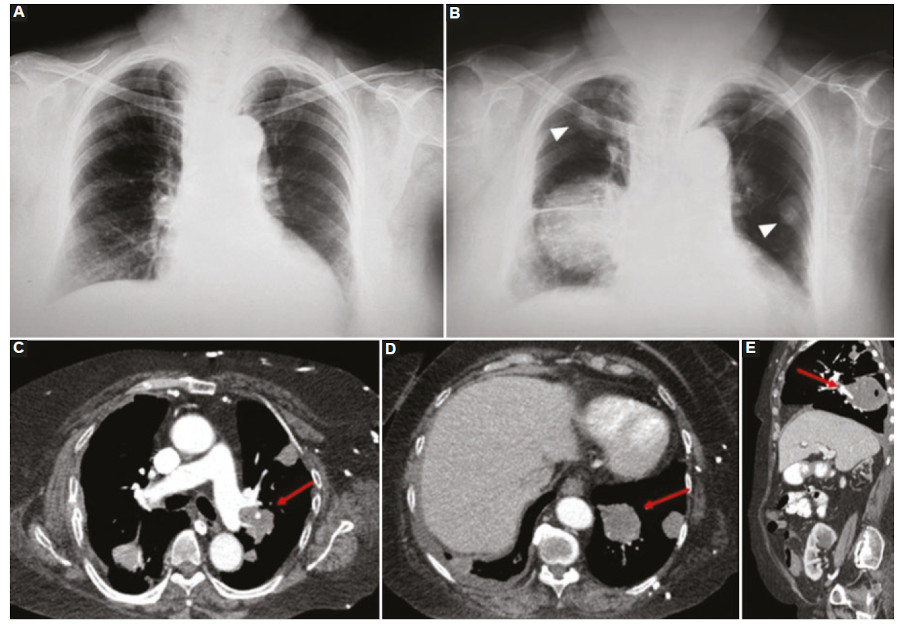

La afectación intratorácica por SLPT es menos frecuente que la abdominal y su incidencia está relacionada fundamentalmente con el tipo de trasplante de órgano, siendo el relacionado al trasplante de pulmón o corazón-pulmón (53% de los casos) el de mayor incidencia8,11.

A nivel torácico el SLPT se puede manifestar como compromiso ganglionar (nodal) con adenopatías mediastinales y perihiliares (7-10%), con masa parenquimatosa única o nódulos pulmonares múltiples (80%), o bien un área de consolidación parenquimatosa (7-10%)11.

Raramente, puede existir una afectación torácica de tipo infiltrativa, desde una lesión intratorácica hacia la pared misma y sus partes blandas, o bien hacia estructuras cercanas. Otras manifestaciones intratorácicas iniciales menos frecuentes son el compromiso pleural, derrame pleural, derrame pericárdico o el aumento del tamaño tímico41.

Cuando la afectación pulmonar se observa como masas parenquimatosas o nódulos sólidos, estos son frecuentemente múltiples, de bordes irregulares o lisos, atenuación homogénea y similar a la de partes blandas en la TC6,11,12) (Fig. 8). Si son múltiples presentan una distribución al azar y raramente pueden presentar halo en vidrio esmerilado o cavitaciones, datos que resultan útiles para un eventual diagnóstico diferencial con las infecciones oportunistas como la aspergilosis42,43.